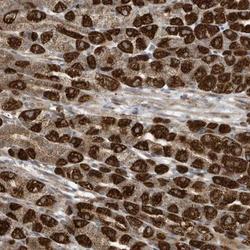

- Main image

- Experimental details

- Immunohistochemistry-Paraffin: C2orf74 Antibody [NBP1-93548] - Staining of human stomach shows strong cytoplasmic positivity in parietal cells.